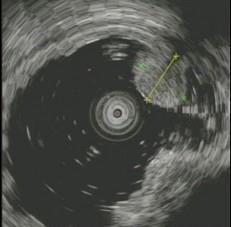

问题 患者,女性,30岁,上腹不适2周,查体:心肺腹未见异常。电子胃镜图片如下,病变部免疫组化CD117阳性,SMA阴性,VIM阳性,诊断为 ( )

选项 A.胃底息肉 B.胃体息肉 C.胃底平滑肌瘤 D.胃体平滑肌瘤 E.胃底间质瘤

答案 E